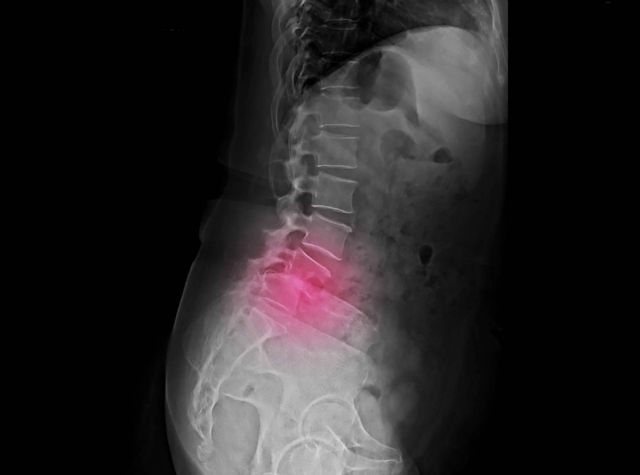

La espondilolistesis es una afección en la cual una vértebra se desplaza saliendo de su posición normal sobre el hueso debajo de ella.

Cuando el deslizamiento se produce hacia adelante, se le llama anterolistesis y si el desplazamiento es hacia atrás se denomina retrolistesis.

Habitualmente, la zona que más se ve afectada por la espondilolistesis es la zona lumbar, específicamente los segmentos L4, L5 y S1. Suele darse con mayor frecuencia en las mujeres y en los mayores de 50 años. Además, cuando el desplazamiento es significativo, puede llegar a causar un atrapamiento nervioso o en casos más severos medular, causando mucho dolor.